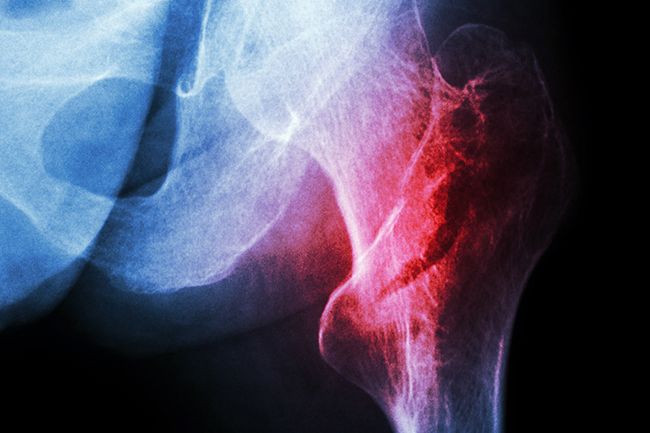

Wir sind zertifiziertes regionales Traumazentrum im Rahmen des Traumanetzwerkes M/V und für die Behandlung von Schwerstverletzten der Berufsgenossenschaften zugelassen (SAV).